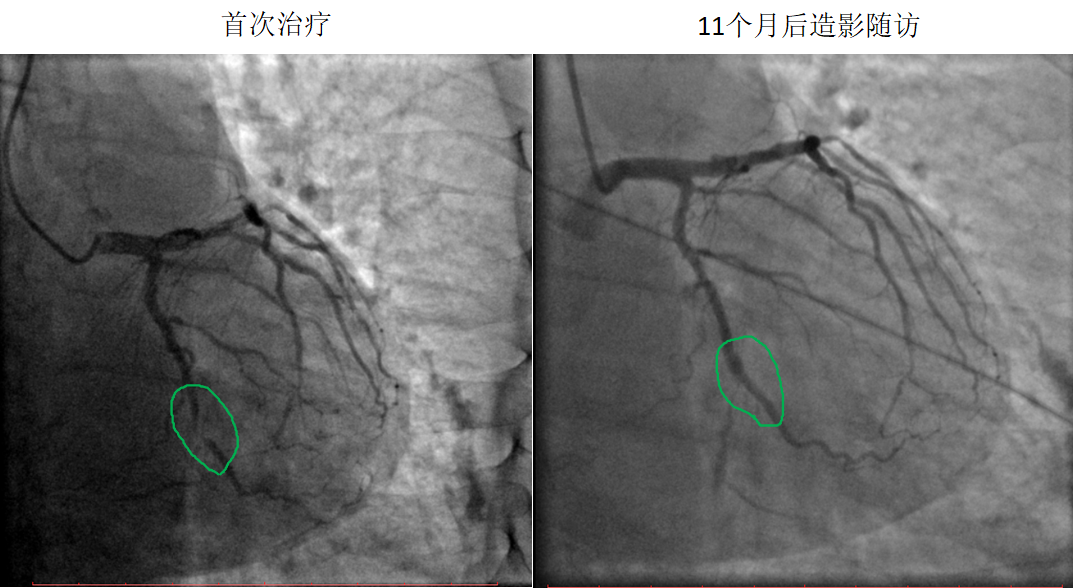

藥物球囊治療閉塞病變

患者:男,51歲

病變部位:LCX中段OM處100%閉塞

使用藥物球囊:2.0 x 20 mm

11個(gè)月后造影

隨訪:LCX中段OM發(fā)出處通暢